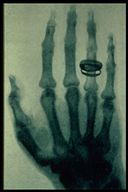

A Century of Radiology

Radiology Centennial Inc., Penn State University Department of Radiology.

http://www.xray.hmc.psu.edu/rci/centennial.html

One of the best of a number of sites celebrating the 100th anniversary of the discovery of the X-ray by Rontgen in 1895. This site describes the history and theory of X-rays, and discusses medical applications of X-rays at length.